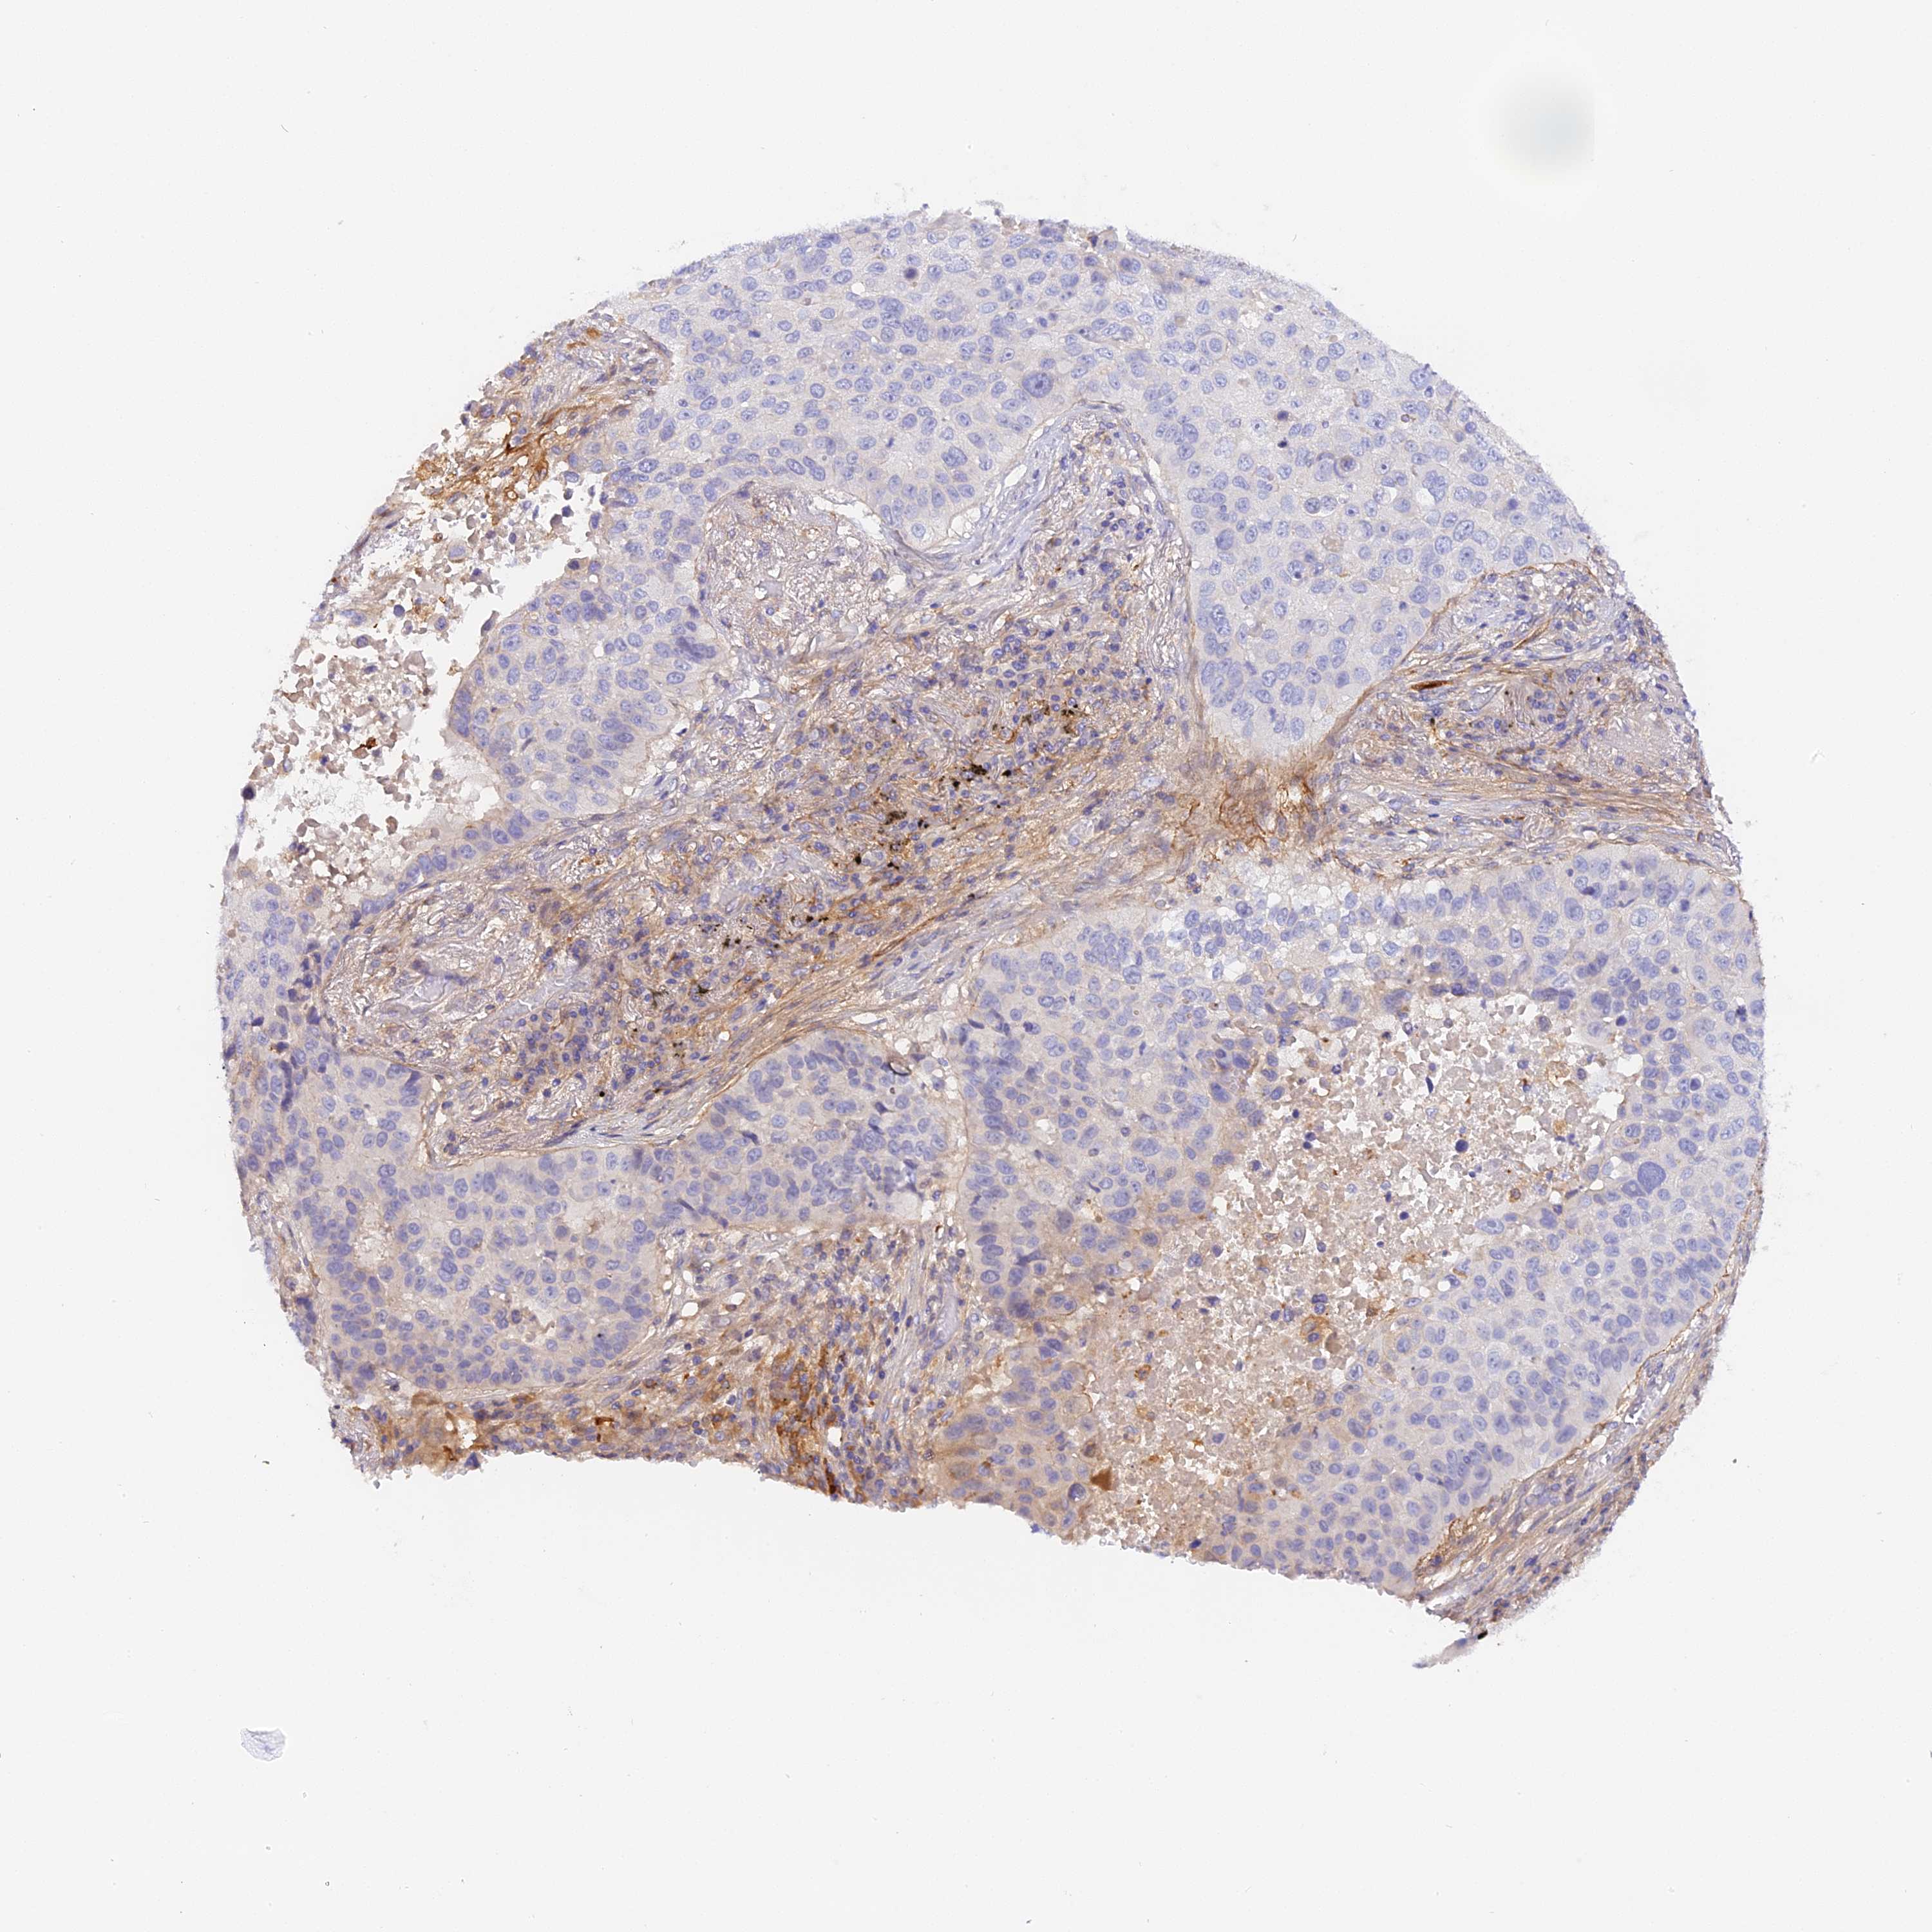

LUNG SQUAMOUS CELL CARCINOMA (TCGA) - Interactive survival scatter ploti

The Survival Scatter plot shows the clinical status (i.e. dead or alive) for all individuals in the patient cohort, based on the same data that underlies the corresponding Kaplan-Meier plots. Patients that are alive at last time for follow-up are shown in blue and patients who have died during the study are shown in red.

The x-axis shows the expression levels (FPKM) of the investigated gene in the tumor tissue at the time of diagnosis. The y-axis shows the follow-up time after diagnosis (years). Both axes are complimented with kernel density curves demonstrating the data density over the axes. The top density plot shows the expression levels (FPKM) distribution among dead (red) and alive patients (blue). The right density plot shows the data density of the survived years of dead patients with high and low expression levels respectively, stratified using the cutoff indicated by the vertical dashed line through the Survival Scatter plot. This cutoff is automatically defined based on the FPKM cutoff that minimizes the p-score. The cutoff can be changed by dragging the vertical line or by entering a cutoff value in the square labeled "Current cut-off".

Under the Survival Scatter plot the p-score landscape (black curve; left axis) is shown together with dead median separation (red curve; right axis). Dead median separation is the difference in median mRNA expression between patients who have died with high and low expression, respectively. It is calculated as follows: median FPKM expression of dead patients with high expression - median FPKM expression of dead patients with low expression. This is intended to aid the user in visually exploring custom cutoffs and the associated p-scores and dead median separation.

Individual patient data is displayed and can be filtered by clicking on one or more of the category buttons on the top of the page. Categories describing expression level and patient information include: high, low, alive, dead, female, male and tumor stages. The scale of the x-axis can be toggled between linear and log-scale by clicking on the "x log" button. Mouse-over function shows TCGA ID, patient information and mRNA expression (FPKM) for each patient.

& Survival analysisi

Kaplan-Meier plots summarize results from analysis of correlation between mRNA expression level and patient survival. Patients were divided based on level of expression into one of the two groups "low" (under cut off) or "high" (over cut off). X-axis shows time for survival (years) and y-axis shows the probability of survival, where 1.0 corresponds to 100 percent.

KATNB1 is not prognostic in Lung Squamous Cell Carcinoma (TCGA)

: 16.22